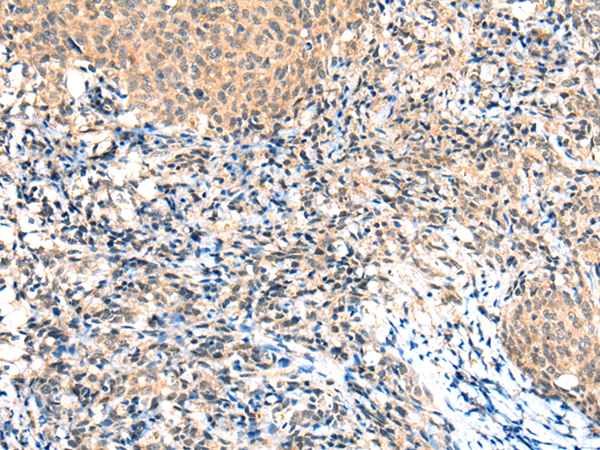

IHC positive control:

Human cervical cancer

IHC Recommend dilution:

25-100

ELISA, IHC